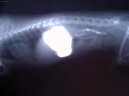

Foto / obrázky k článku  Léčba interních onemocnění